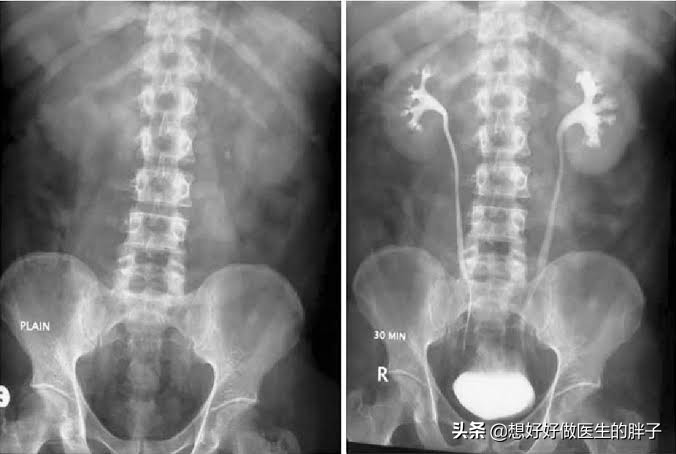

●左侧腹部疼痛的原因比较常见的是肾结石和输尿管结石,其实输尿管并不是在腹部内的脏器,但如果输尿管有结石造成了输尿管的痉挛,会表现出来明显的左侧腹痛。有结石的时候会造成输尿管的不通畅,会导致肾盂积水,患者往往还会表现出肾脏的闷痛,有的患者会出现腰部的疼痛。有些患者尿液会变深甚至变红,这是由于有结石刺激到了输尿管的内部,有少量的渗血导致的,部分患者因为输尿管的问题,疼痛会放射到左下腹部以及腹股沟区。

输尿管的问题往往要进行彩超检查、CT检查或者是静脉肾盂造影等来明确问题。